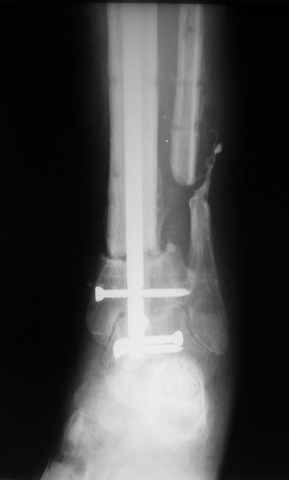

Рентгенограммы прилагаются. Фото местного статуса выложу в ближайшее время.

Мы обычно не фиксируем малоберцовую кость. Просто стараемся сопоставить ее концы за счет хорошей репозиции. В представленном случае имеется некоторое смещение дистальных фрагментов кнаружи, и, как мне кажется, ротация их вместе со стопой кнутри (ротация хорошо заметна на прямом снимке по форме таранной кости и на боковом по соотношению отломков малоберцовой). Если это действительно так, то это несложно сейчас постепенно устранить в аппарате. И тогда концы малоберцовой кости будут находиться поближе друг к другу.

Ерсин, мы тоже имеем опыт такой фиксации. Подобную операцию за последние 3 года мы сделали трем пациентам. Снимки одного из них я прилагаю.

К сожалению, ни в одном из этих 3-х случаев мы не получили удовлетворяющего нас результата. Очень трудно провести штифт, введенный антеградно ровно по центру таранной кости. Отсутствие подвижности между диафизом и дистальным отломком большеберцовой кости (после фиксации в аппарате в течение 1-2 мес) очень усложняет проведение штифта в центр блока таранной кости. Поэтому мы от этого пока отказались, и проводим штифт через пятку. При данном варианте фиксации подобных проблем не возникало ни разу.